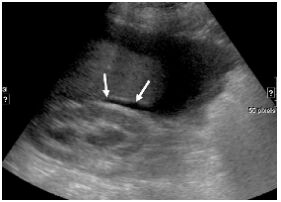

22.患者接受大腸鋇劑灌腸(barium enema)攝影的結果如下圖,最可能是下列何種疾病?(A)腸套疊 (B)惡性腫瘤 (C)腸扭轉 (D)腸炎